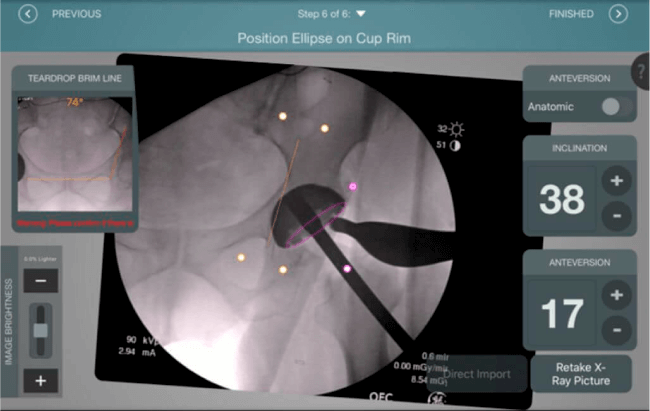

El sistema de navegación digital VELYS HIP NAVIGATION ™ para cirugía de cadera, es una tecnología innovadora y no invasiva diseñada para potencializar la toma de decisiones en tiempo real y basada en datos; aumentando la precisión y mejorando los resultados a corto, mediano y largo plazo para los pacientes.

Inclinación y anteversión de la copa acetabular para una correcta colocación del implante.

Verificación de la posición deseada del implante que potencialmente puede ayudar a reducir la probabilidad de dislocación protésica y aumentar la estabilidad de la articulación.